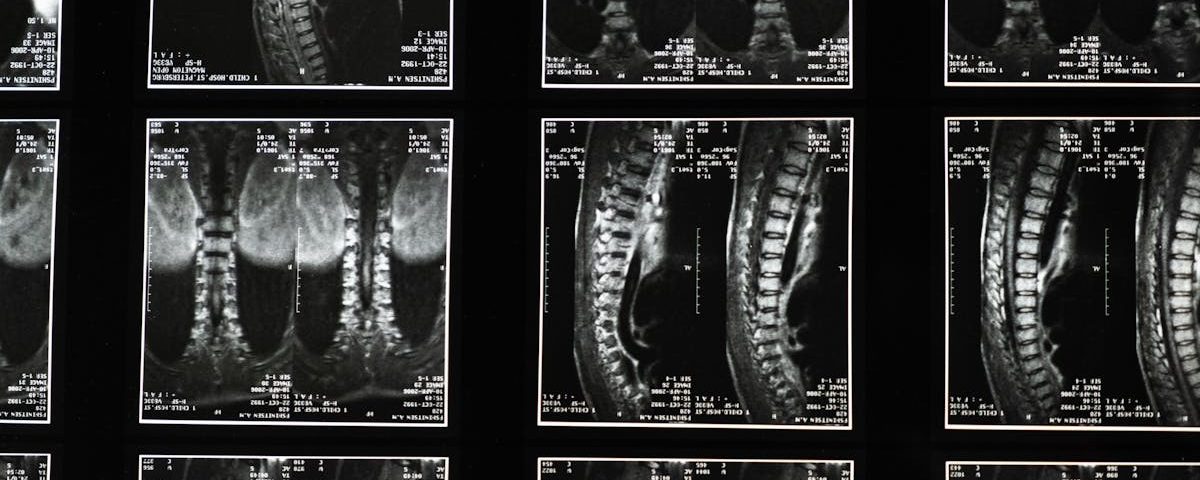

La sciatique est une condition caractérisée par une douleur qui se propage le long du nerf sciatique, du bas du dos jusqu’aux jambes. Cette affection résulte souvent d’une compression des racines nerveuses lombaires, ce qui provoque des douleurs intenses pouvant être invalidantes. Comprendre les facteurs contribuant à cette condition est essentiel, notamment le rôle du stress dans la gestion de la douleur.